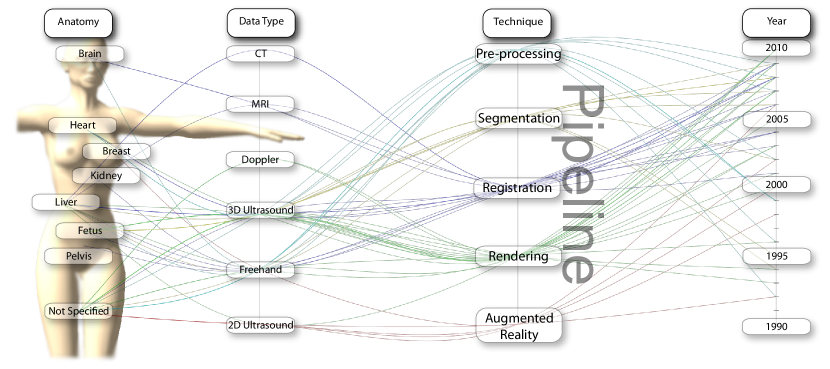

Techniques for ultrasound visualization can be categorized in a variety of ways, e.g, when they where developed, what types of data modalities was utilized, which anatomy the technique was focused on, etc. The development of new ultrasound technology leads to different visualization techniques. The step from 2D ultrasound images to 3D freehand ultrasound (2D ultrasound with position information) revealed new challenges as spatial information could be included to generate volumetric data. The recent development of 2D matrix probes provided again a new challenge of 3D + time (4D) data visualization. Karadayi et al. published a survey regarding 3D ultrasound karadavi09 . This paper has a greater focus on data acquisition and volume handling, but also give a brief overview over visualization of 3D ultrasound data.

Another taxonomic scheme for ultrasound visualization is based on the different types of data the technique utilized. 3D Freehand and 4D ultrasound, pose very different challenges compared to 2D ultrasound or when handling multiple modalities. Blending b-mode ultrasound for tissue and color-doppler ultrasound for blood flow can be challenging enough in 2D if not in 3D. An example image is shown in Figure 1d. In addition to the ultrasound input, the combination of other medical imaging modalities, such as CT or MRI with ultrasound, provide more information, but also more challenges to the visualization researcher.

Different anatomic regions have different characteristics in ultrasound images, as can be seen in Figure 1. For instance, in a liver scan one might look for tumors using a high-resolution abdominal 2D probe. For heart infarctions, the doctor might need to examine the strain in the heart muscle to detect defect muscle tissue. The wide spread in tissue and pathology difference lead to anatomically specific visualization techniques.

In this survey we categorized around 60 papers and from the different categories we generated a parallel-coordinate plot, show in Figure 2. Looking at the graph, we see an increase in rendering techniques for 3D ultrasound in the last five years. Volume rendering is often considered to be a solved problem. However, our study shows that much work dealt with volumetric ultrasound data. Yet, 3D ultrasound rendering can still not be considered a solved problem. The high presence of noise, shadows from hyper-echoic areas and inconsistent data values provide a great challenge to make 3D ultrasound a more easy-to-use tool for examiners.

We also see an absence of augmented reality techniques for 3D ultrasound. Yet another trend is the neglecting of 2D ultrasound from the visualization community. 2D ultrasound is the most used modality by physicians and while presenting the signal data onto the screen is straight forward, understanding what you see is not so trivial. Increasing the readability of 2D ultrasound is mostly worked on in the commercial domain, aiming to give the company an edge over its rivals.

In Figure 2 we see the categorized papers in a parallel coordinate plot where each axis corresponds to the different taxonomy classification. The second axis (the pipeline axis) is selected as the classification for this survey. Five categories where chosen based on what we recognize as the essential parts in the visualization pipeline for ultrasound data: